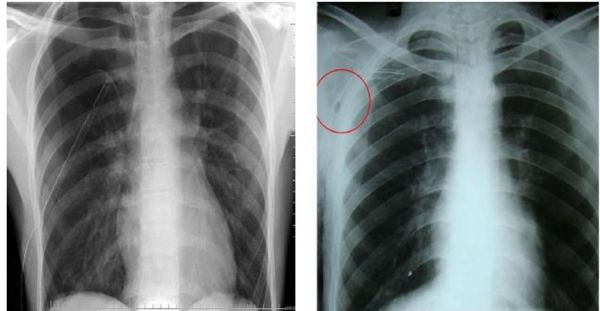

Chụp X-quang ngực là ảnh chụp lại phần ngực bằng tia X-quang, trong phim chụp bác sĩ sẽ thấy được hình ảnh của tim, phổi, đường thở, mạch máu và hạch bạch huyết. Chụp X-quang ngực còn cho thấy xương cột sống và các xương ngực, bao gồm xương ức, xương sườn, xương đòn và phần trên cột sống. Chụp X-quang ngực rất thường được sử dụng để tìm những bất thường bên trong lồng ngực.

Kết quả bình thường:

Phổi bình thường về kích thước, hình dáng và mô phổi bình thường. Không có biến chứng hay khối nào trong phổi. Màng phổi bình thường. Tim bình thường về kích thước, hình dáng và mô tim bình thường. Mạch máu dẫn tới và ra khỏi tim bình thường về kích thước, hình dáng và vẻ ngoài. Xương sống và xương sườn bình thường. Cơ hoành bình thường về hình dáng và vị trí. Không tìm thấy sự tích tụ chất lỏng hay khí, và không có sự xuất hiện vật lạ. Các loại ống, ống soi hay vật dụng y tế ở đúng vị trí trong phổi.

Kết quả bất thường:

Phát hiện viêm nhiễm như viêm phổi, bệnh lao. Phát hiện những vấn đề như khối u, chấn thương, phù phổi do suy tim. Trong vài trường hợp, cần thực hiện chụp X-quang hay kiểm tra bổ sung để tìm hiểu sâu hơn. Phát hiện vấn đề về hở tim gây ra do tổn thương tim, bệnh van tim, hay tràn dịch màng tim. Hay phát hiện ra vấn đề về mạch máu như hở động mạch chủ, chứng phình động mạch, xơ cứng động mạch. Phát hiện dịch quanh phổi (phù phổi) hay khí xung quanh (khí tràn màng phổi). Phát hiện gãy xương ở xương sườn, xương đòn, xương vai hay cột sống. Phát hiện hạch to. Phát hiện vật thể lạ trong thực quản, ống thở hay phổi. Các loại ống, ống soi hay vật dụng y tế không ở đúng vị trí trong ngực.